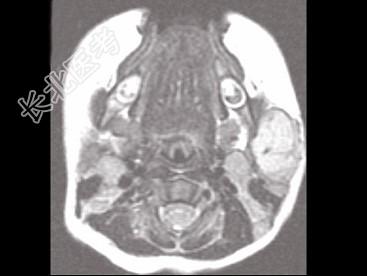

- 单项选择题男,40岁, 左面部渐进性增大的包块,MRI检查如图所示, 最可能的诊断是 ( )

A、左面部毛细血管瘤

B、左面部囊肿

C、左面部脓肿

D、左面部脂肪瘤

E、左面部神经纤维瘤